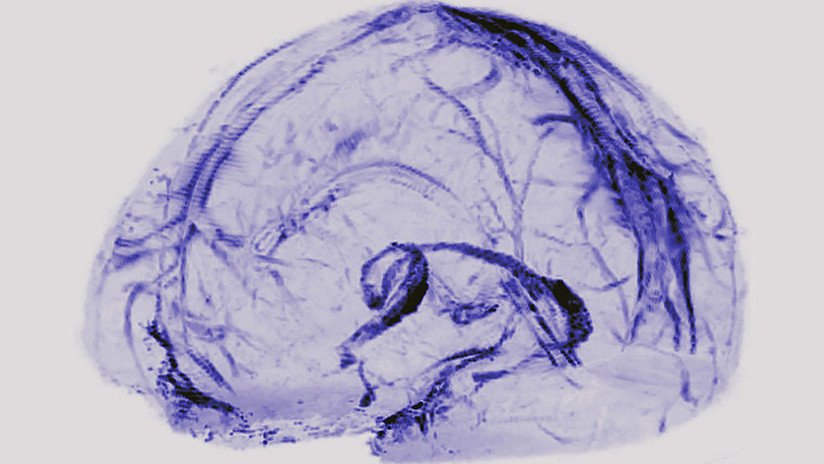

¿Tenemos órganos que no resultan indispensables para sobrevivir? Si bien todos cumplen alguna función útil, algunos pueden ser extirpados sin provocar un gran impacto sobre nuestra salud. De hecho, pocas personas conocen que nos podemos adaptar a la pérdida de grandes partes del cuerpo, como la mitad de la masa cerebral.